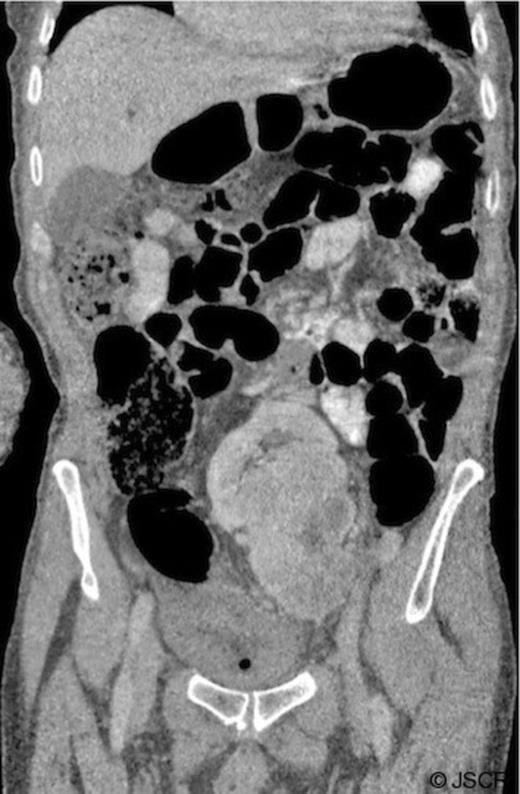

On abdominal examination, there was a mass palpable in the left iliac fossa, which was initially thought to be an intra-abdominal malignancy and therefore a computed tomography (CT) scan of the abdomen and pelvis was arranged. This demonstrated a normal right kidney, absence of a normally positioned left kidney and a complex solid lobulated 11 x 7 cm mass arising from a presumed left pelvic kidney (Figure 1).

CT of the abdomen and pelvis with oral and intravenous contrast. Coronal image showing a reniform mass in the central pelvis: a presumed left pelvic kidney with a complex heterogenous mass arising and extending inferiorly.